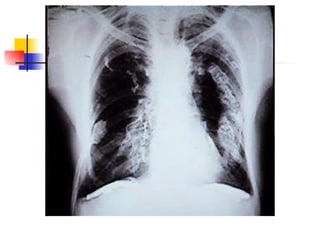

Cuadro radiológico característico: - profusa infiltración - consolidación miliar A largo plazo: - pequeñas opacidades redondeadas en  lóbulo superior - linfadenopatías hiliares (15-20 años exposición) - calcificación con aspecto “cáscara de huevo”

Cuadro radiológico característico:- profusa infiltración - consolidación miliar A largo plazo: - pequeñas opacidades redondeadas en lóbulo superior - linfadenopatías hiliares (15-20 años exposición) - calcificación con aspecto “cáscara de huevo”